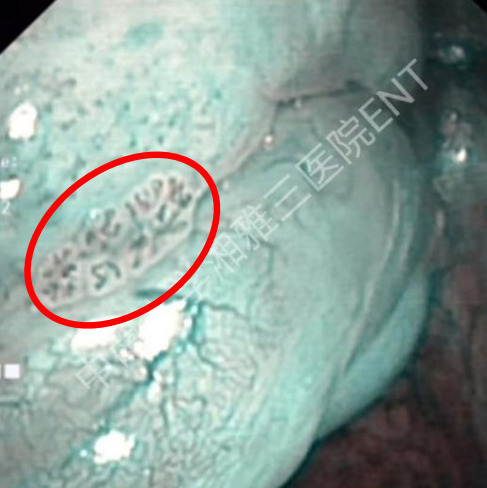

(窄带成像内镜下喉部肿瘤血管呈棕褐色形态、呈蝌蚪或蚯蚓状)

窄带成像内镜检查方式与普通内镜一样,安全无辐射,检查时间短,在癌症发生的早期,NBI内镜可以使黏膜表面的微小血管呈现棕褐色,与周围淡绿色背景黏膜形成鲜明对比,根据微小血管形态改变,从而鉴别肿瘤性和非肿瘤性病变,其精准度明显高于普通内镜,并与病检结果具有较好的一致性。